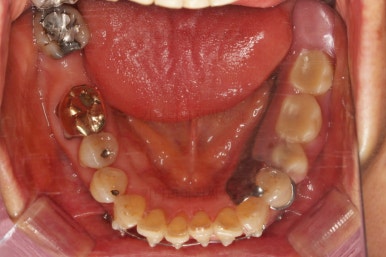

초진 시 입안의 모습입니다.

일반적인 교정을 하기에는 적합한 모습은 아니었어요.

치아는 군데군데 없고 임플란트도 있고 브릿지로 연결된 치아도 있으며 전반적인 잇몸 상태도 좋지 못했어요.

앞니가 벌어져 있고 뻗쳐 있으며 잇몸에서 쏙 빠져나와 있는 듯한 느낌이었어요.